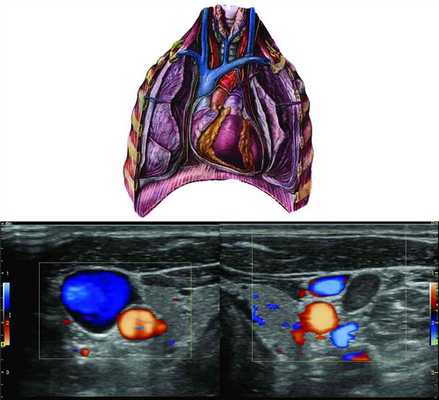

В то же время если оценка кровотока по венам затруднительна (особенно при наличии клапанов и значительном влиянии дыхательных экскурсий), размеры яремных вен, особенно при сканировании в поперечной плоскости на уровне нижней трети серии, измеряются довольно точно (рис. 1, см. на цв. вклейке). Рисунок 1. Обоснование асимметрии яремных вен. На ультразвуковых ангиограммах синим цветом окрашен кровоток в яремных венах. Отмечается асимметрия вен за счет расширения справа на 9 мм, более тесное прилежание правой яремной вены к сонной артерии.

Ультразвуковое ДС нижней трети шеи, особенно при поперечном расположении датчика, показало увеличение размеров луковицы правой яремной вены от 2 до 9 мм (см. рис. 1 на цв. вклейке) у 82% здоровых людей. Наиболее значительное преобладание размеров правой яремной вены по сравнению с левой фиксировалось на высоте пробы Вальсальвы, что еще раз подчеркивает значительное влияние дыхательных экскурсий на венозный отток. Такая асимметрия выявлялась у 95% добровольцев с видимым при осмотре усилением пульсации справа. Иными словами, ДС не только подтвердило заметную на глаз асимметричную пульсацию яремных вен, более выраженную справа (в среднем на 3,5±2,6 мм в положении лежа в покое), но и выявило ее значительно более высокую (82% обследованных) распространенность, что говорит о высокой чувствительности ультразвукового метода.

Сходными с результатами ДС оказались данные анализа инфракрасного излучения в надключичных областях: у подавляющего большинства обследованных с умеренными или выраженными пульсациями в правой надключичной области выявлялась четкая гипертермия с «разогревом» правой надключичной области над проекцией луковицы яремной вены (см. таблицу). Эта анизотермия особенно ярко проявлялась у долихоцефалических людей молодого возраста (рис. 2, см. на цв. вклейке). Рисунок 2. «Разогрев» на термограмме в правой надключичной области - в зоне проекции расширения луковицы гомолатеральной яремной вены, выявленный при дуплексном сканировании. Показательно, что корреляция между степенью анизотермии и выраженностью асимметрии луковиц яремных вен при дуплексном сканировании составила R=0,56 (p<0,01).